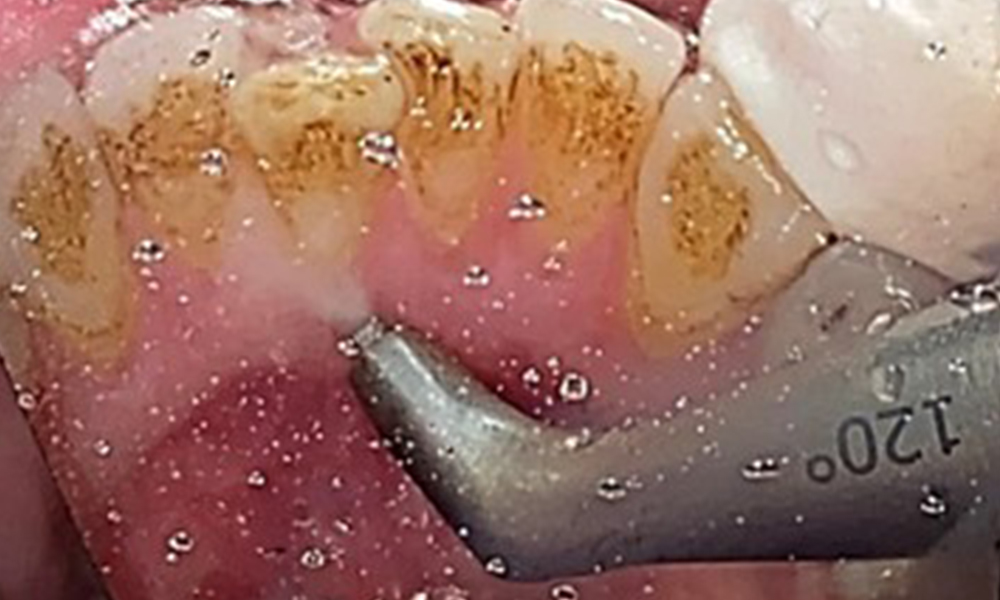

The objective would be to control disease risk by removing supragingival and subgingival biofilm. The instruments can be selected based on patient needs. First, calculus and any concretions must be removed using ultrasonic and/or manual instruments (Fig. 10).

Discolouration caused by nicotine and tea consumption can be removed easily using an air polisher (Fig. 11).